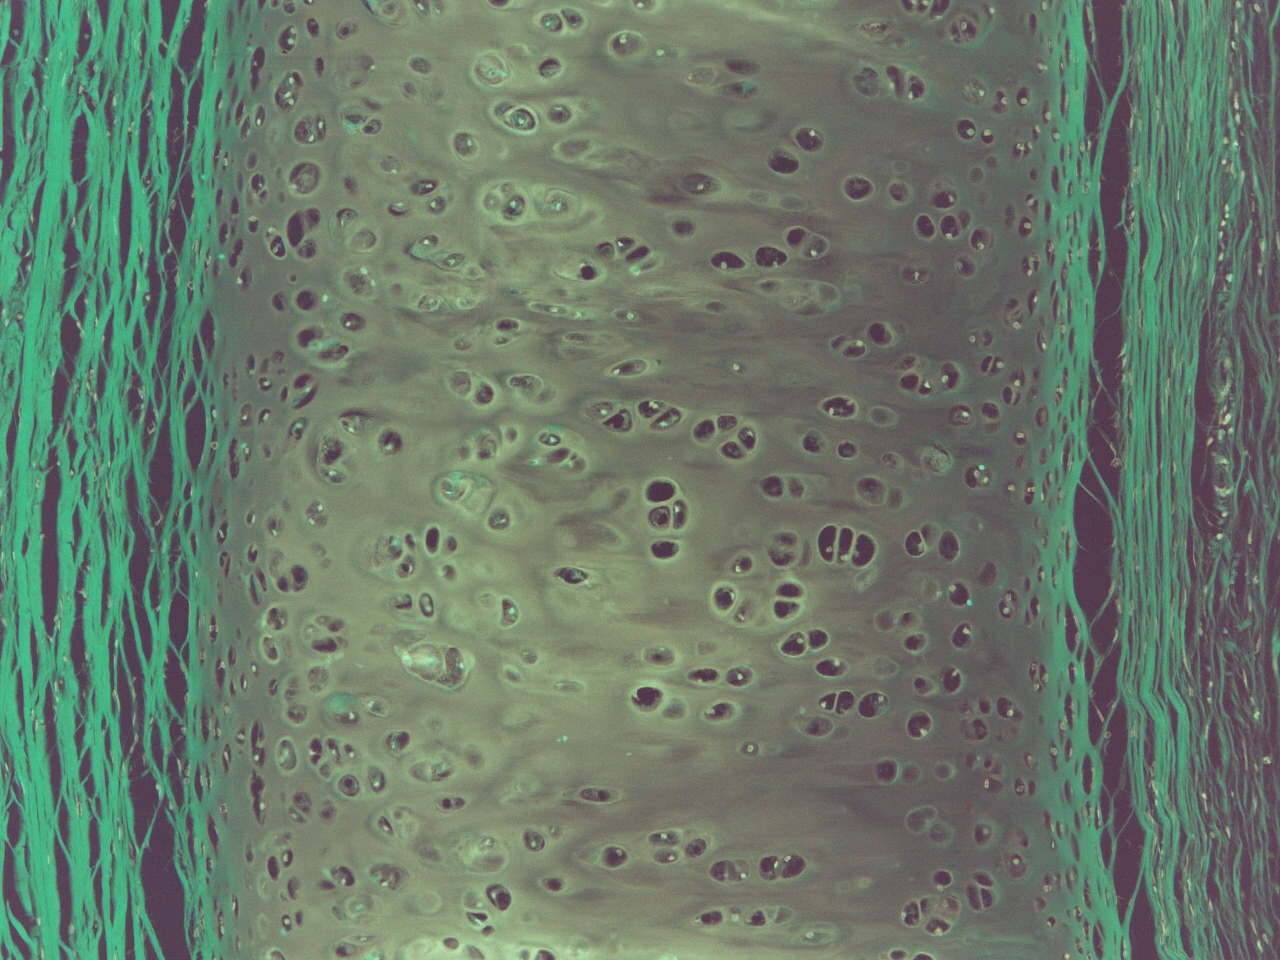

Niniejszym mamy przyjemność poinformować, iż decyzją Ministerstwa Zdrowia oraz Polskiego Towarzystwa Patologów Zakład Patomorfologii Klinicznej i Doświadczalnej Collegium Medicum Uniwersytetu Jana Kochanowskiego w Kielcach otrzymał Certyfikat Akredytacyjny oraz licencję o stopniu referyncyjności II na wykonywanie badań histopatologicznych, histochemicznych, immunohistochemicznych, śródoperacyjnych, cytologicznych oraz sekcyjnych.

Akredytacja oraz Licencja otrzymana przez Zakład Patomorfologii Klinicznej i Doświadczalnej Collegium Medicom Uniwersytetu Jana Kochanowskiego w Kielcach jest wyrazem uznania dla funkcjonujących procedur oraz wysokiej jakości badań wykonywanych przez naszą placówkę.